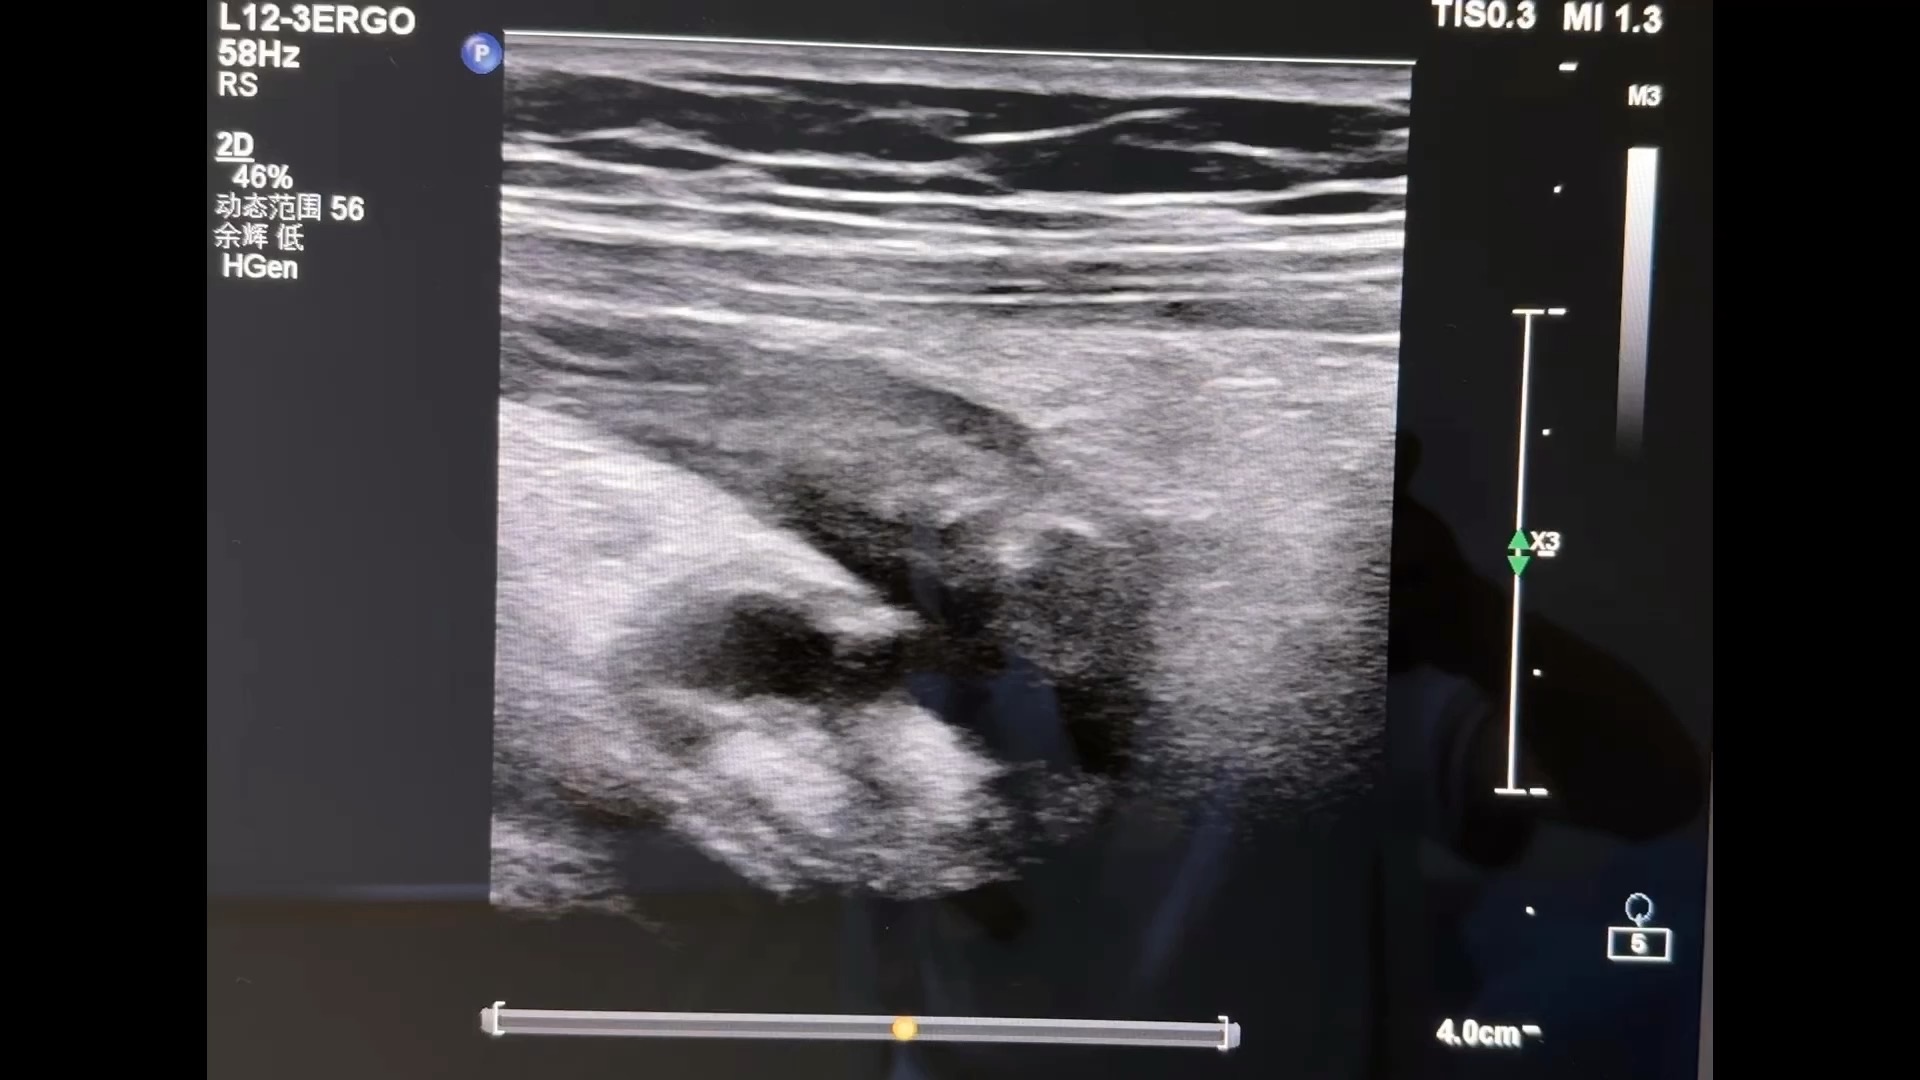

女,4岁,脐周疼痛,右下腹压疼,做超声的过程中感觉肚子胀胀的有点肌紧张。首先看到下腹部网膜增厚,于是加压探头看了到有问题的阑尾。

又对患儿增加了压力看到阑尾起始部和一枚粪石。